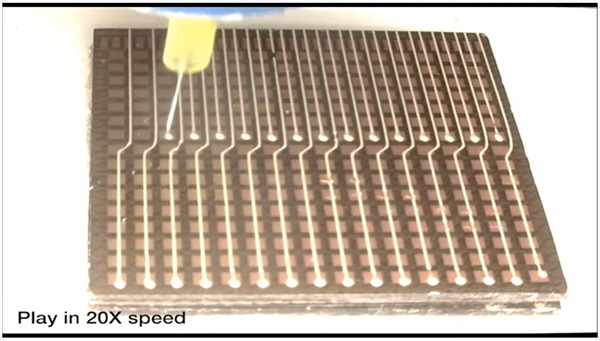

MIT 팀의 새로운 초음파 스티커는 신축성 있는 접착층을 단단한 변환기 배열과 결합해 더 긴 시간 동안 고해상도 이미지를 생성한다. 왕 연구원은 “이러한 조합은 변환기의 상대적인 위치를 유지하면서 장치가 피부에 적합하도록 해 더 선명하고 정확한 이미지를 생성할 수 있게 해 준다”고 설명했다.

이 초음파 장치의 접착층은 주로 음파를 쉽게 전달하는 수성 물질인 고체 하이드로겔의 중간층을 감싸는 두 개의 얇은 탄소중합체(실리콘 고무같은 합성 고무) 층으로 만들어졌다. 기존의 초음파 젤과 달리 MIT 팀의 하이드로겔은 신축성을 갖는다.

MIT 포스트닥인 첸은 “탄성중합체는 하이드로겔의 탈수를 예방해 준다. 하이드로겔이 수분을 많이 공급받을 때에만 음파가 몸속 장기에 효과적으로 침투해 고해상도 영상을 제공할 수 있다”고 설명했다.

하단 탄소중합체 층은 피부에 달라붙도록 설계됐으며, 윗 층은 MIT 팀이 설계 제작한 견고한 변환기 배열에 부착된다. 전체 초음파 스티커의 크기는 작은 우표 정도인 약 2c㎡에 두께는 약 3mm다.